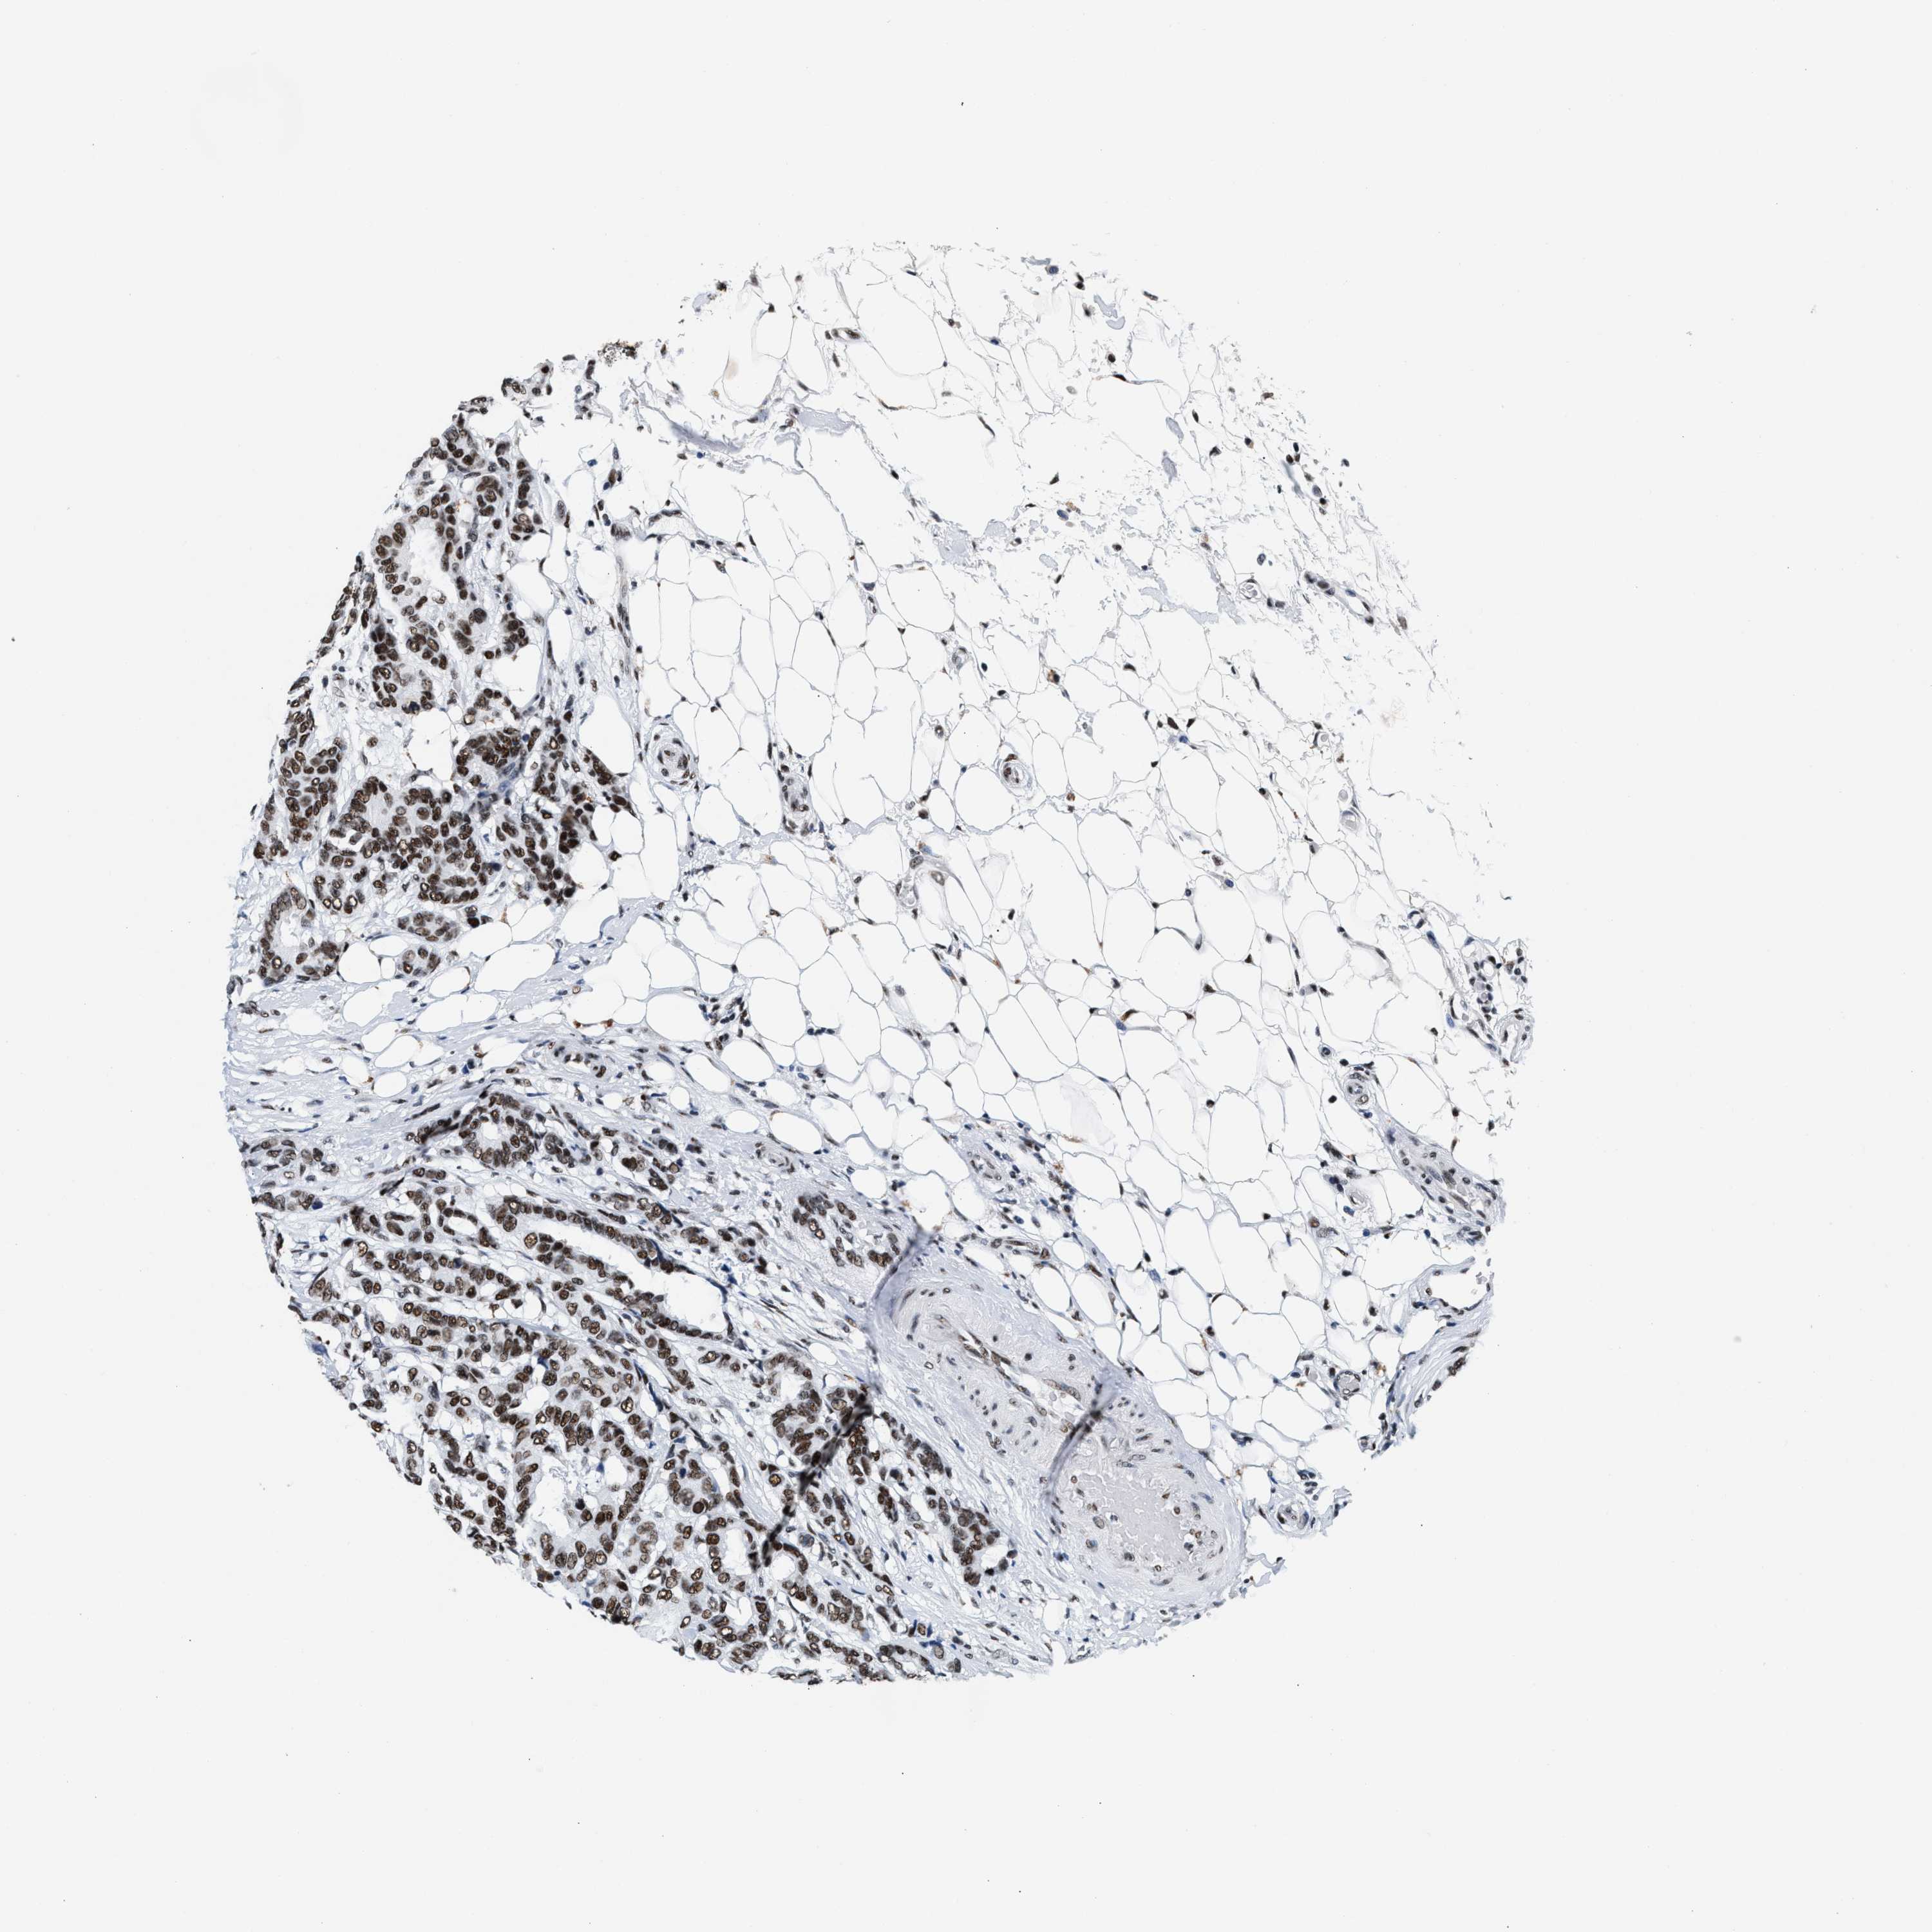

BRCA TCGA BRCA VALIDATION PROTEIN EXPRESSION